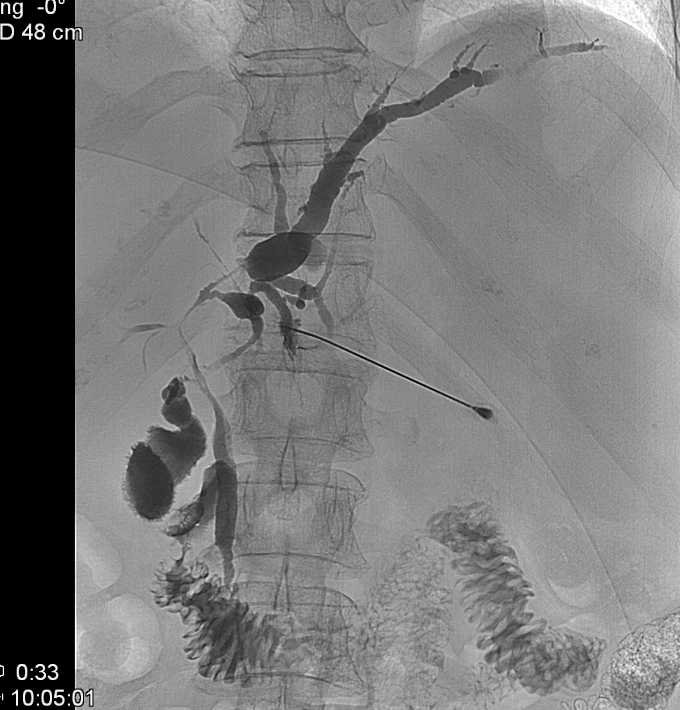

The percutaneous contrast filling of the biliary ducts can be necessary if no reassuring diagnosis was made by US, CT or MRI scans, or the ERCP implementation was unsuccessful due to a technical obstacle (Billroth II. gastric resection, choledochojejunostomy), or the canulation of the papilla of Vater was technically failure. PTC can be only performed in case of appropriate bleeding or coagulation status. (Figure 9) .

Figure 9: PTC (Percutaneous transhepatic cholangiography)

Significant amount of free abdominal fluid is also a relative contraindication. In the course of PTC, the liver punction is usually performed in the 9th or 10th rib spaces under fluoroscopic guidance using a 22 G Chiba needle. The punction should be guided towards the liver hilum. US guidance is helpful in the easier puncture of dilated or even peripherially located biliary ducts. The entire biliary system can be filled through this puncture. Following the diagnostic biliary duct contrast administration – after a previous consultation – bridging of the detected biliary stenosis can be performed (PTC-PTD, biliary duct stenting). Moreover, percutaneous stone extraction can be carried out if necessary.